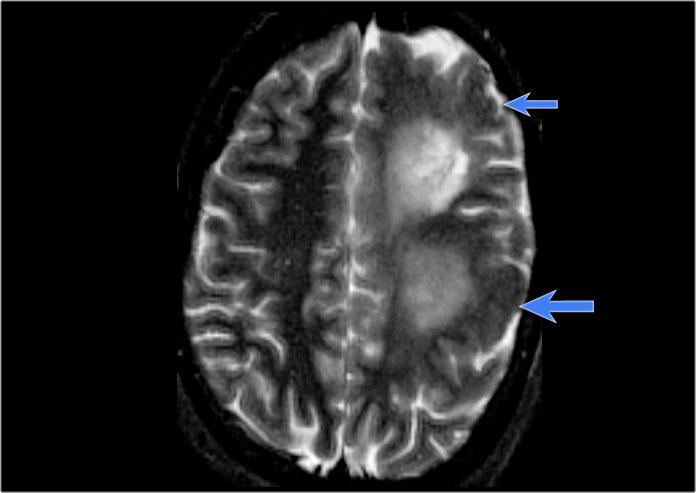

Hình ảnh của bệnh nhân nam 27 tuổi bị động kinh thùy chẩm kháng trị.

Ảnh FLAIR mặt phẳng coronal và T2W mặt phẳng axial cho thấy dày vỏ não tăng tín hiệu T2 và tăng tín hiệu ở vỏ não và vùng dưới vỏ.

Lưu ý vùng tăng tín hiệu dưới vỏ kéo dài đến não thất bên phải, biểu hiện dấu hiệu xuyên vỏ (mũi tên xanh).

Dấu hiệu xuyên vỏ (transmantle sign) ghi nhận ở một bệnh nhân khác bị loạn sản vỏ não khu trú.